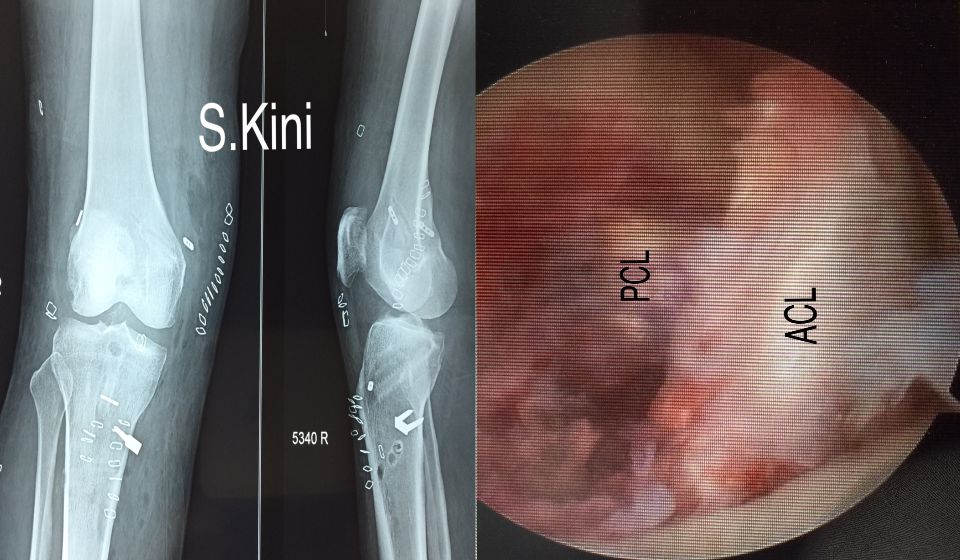

A small camera is inserted into the knee and the images are relayed to a television screen.

- The Cruciate ligaments are 2 strong ligaments, the anterior and the posterior, which provide stability of the knee on twisting and pivoting activities. They are often injured in contact sports and skiing. Arthroscopy allows a clear view and physical inspection of the Cruciate ligaments and gives us the opportunity to reconstruct them if necessary.